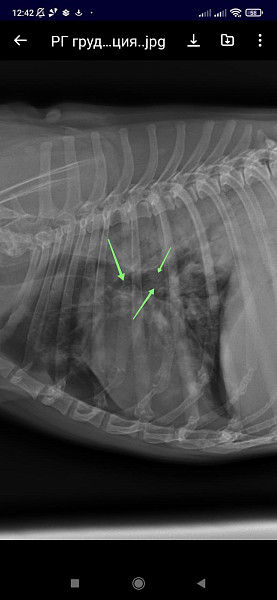

Добрый день!собачка кобель цвергпинчер 14 лет 10 месяцев,стал часто дышать,сделали рентген,помогите понять что с ним!

Ренген

Добрый день!ренген лёгких у собаки помогите прояснить ситуацию!сделали в связи с частым дыханием

Здравствуйте, у собаки выраженное затемнение по каудальным долям легких. Более всего это похоже на пневмонию.